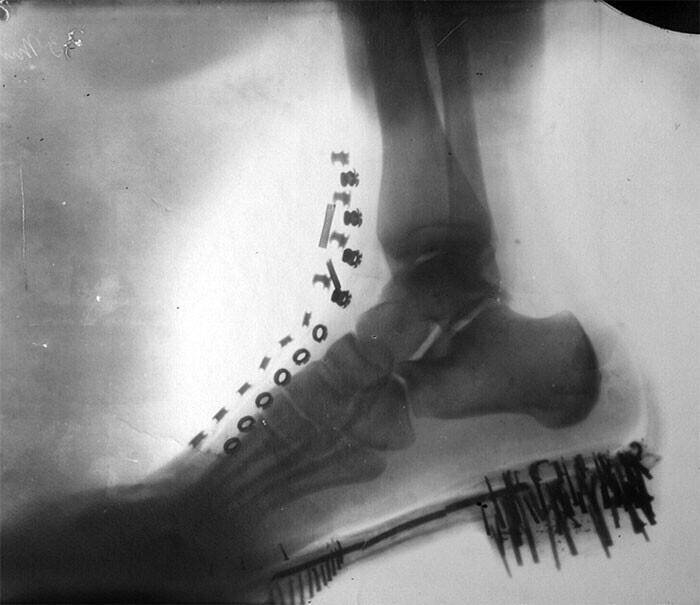

Нога Николы Тесла на рентгеновском снимке, сделанный им самим на аппарате собственной конструкции, США, 1896 год.

Существует версия, что Никола Тесла открыл рентгеновское излучение раньше, чем Вильгельм Рёнтген.

В 1887 он проводил эксперименты с электричеством и обнаружил лучи, невидимые для невооруженного глаза. Эти лучи могли проходить через некоторые предметы и обнаруживать другие. Это величайшее открытие Никола Тесла не запатентовал, или не придал ему значения, но в 1895 году Вильгельм Рентген тоже обнаружил эту особенность и создал рентгеновский аппарат.